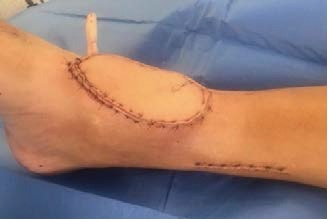

How will my Soft Tissue Reconstruction change over time?

Soft tissue reconstruction, especially involving muscle, always looks bit bulky at start.

However, as the flap matures over time, its volume reduces. It usually levels with the tissue around it but can sometimes remain a bit bulky.

The colour of the flap changes over time to more or less match the skin next to it. The size and colour change is a process that takes time to settle, usually 9-12 months.

The pictures below show a timeline of a muscle flap immediately after the operation (left), after 3 months (right), and after 9 months (bottom).

Very occasionally, any bulkiness that remains can be treated, if necessary, with secondary procedures.